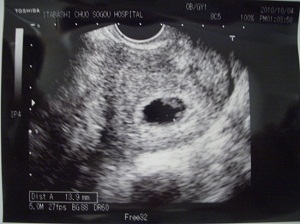

心臓が動いているのがはっきりわかりました。卵黄嚢も見えてます。 現在9.4ミリだそうです。 次は2週間後ですが、正直毎週見たいぐらいです!

頭殿長13.9mm。